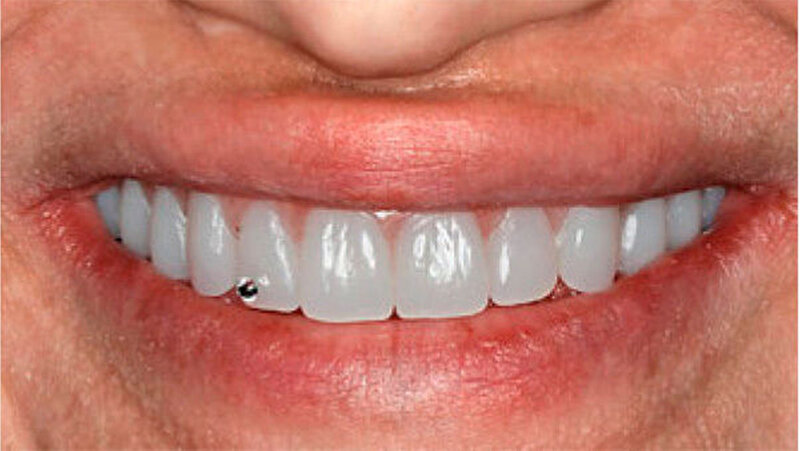

Die Patientin war mit einer knapp neunjährigen Teilprothese im Ober- und einer zweijährigen Totalprothese im Unterkiefer versorgt. Beim Lachen wurden die nicht mehr altersentsprechenden Prothesenzähne mit den deutlichen Randverfärbungen ersichtlich (Abb. 19). Das sagittale Wachstum des zahnlosen Unterkiefers führte in den letzten zwei Jahren aufgrund der verstärkten Kontakte im Frontzahnbereich zu einer beidseitigen Nonokklusion im Seitenzahnbereich (Abb. 20). Eine rasche Verbesserung der Ästhetik als auch der Funktion war unbedingt angezeigt, um das Selbstbewusstsein dieses puberalen Mädchens zu stärken.

Aufgrund des anatomisch sehr ungünstigen Prothesenlagers war der Erhalt der Restbezahnung im Oberkiefer anzustreben. Nach Kariesexkavation und Wurzelkanalbehandlung konnten beide Zähne mit einer Wurzelstiftkappe versorgt und die alten Prothesen entsprechend umgebaut werden. Im Anschluss an die Meisterabformungen und an die Ausrichtung der Wachswälle wurden die Modelle schädelbezogen einartikuliert, und die Prothesenzähne nach ästhetischen und funktionellen Richtlinien aufgestellt. Eine bilateral balancierte Okklusionsbeziehung konnte umgesetzt werden. Im Oberkiefer wurde eine gerüstverstärkte Totalprothese hergestellt, die auf den beiden Wurzelstiftkappen 16 und 26 verankert war. Im Unterkiefer konnte die Patientin mit einer Totalprothese versorgt werden (Abb. 21 bis 23).

Verbunden mit dem Umstand, dass die Patientin eine ausgeprägte Oligosialie aufweist, ist das Kariesrisiko und hiermit verbunden, auch das Pfeilerzahnrisiko deutlich erhöht. Regelmäßige Kontrolluntersuchungen sind zwingend. Da das Kieferwachstum noch nicht abgeschlossen ist, werden weitere zahnärztliche Behandlungen unumgänglich sein. Diese wenig invasive und relativ zeitnah umsetzbare Therapie erlaubte jedoch eine deutliche Verbesserung der Funktion und der Ästhetik und führte zu einer sichtlichen Stärkung des Selbstbewusstseins. Weitere zukünftige aufwendigere Behandlungsoptionen - insbesondere implantatgetragene Restaurationen - können nun nach abgeschlossenem Wachstum, auf der Basis einer ästhetisch und funktionell akzeptablen Ausgangslage, im Behandlungsteam geplant werden.